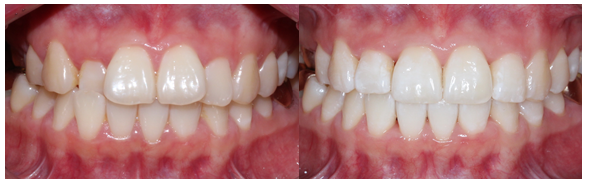

마무리 한 모습입니다.

브라켓을 붙이고 진행한 것은 아니라

디테일하게 중심선을 맞추거나

구치부 교합까지 완벽히 잡진 못하지만

환자분께서 원하시던

#12가 들어가 있던 모습과

뻗쳐보이는 느낌을 개선 후 마무리를 했습니다.

이렇게 투명교정을 통해

골격적 비대칭을 완벽히 해소하진 못해도

가지고 있는 골격 안에서

최대한 환자분의 니즈에 맞춰

교정을 할 수 있습니다.